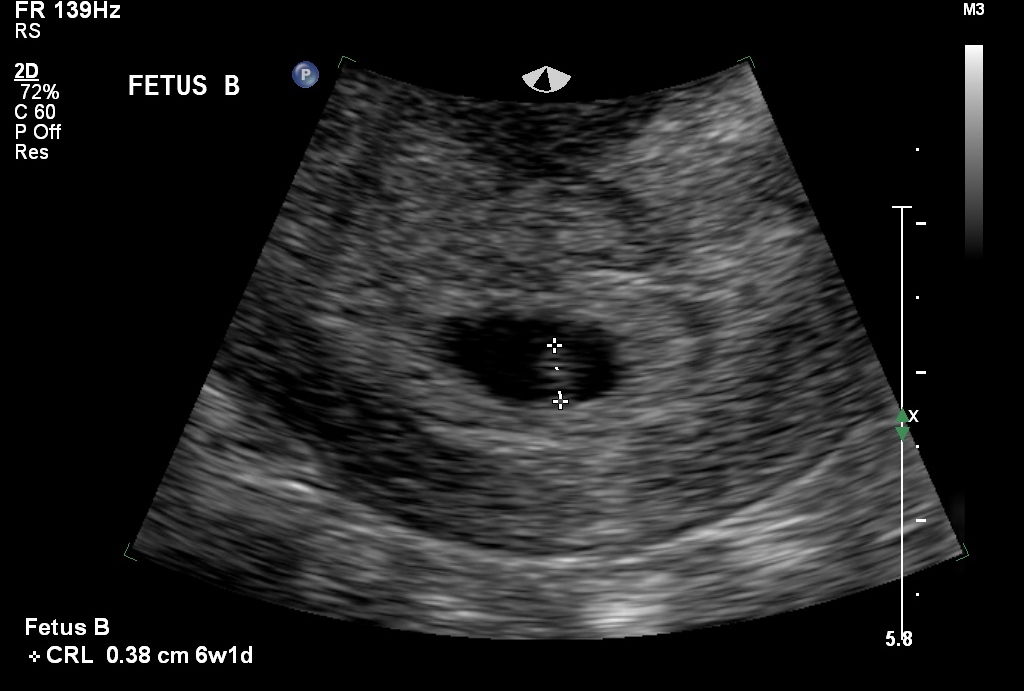

Everything looked good.  We got to see the heartbeats, but they were too small to hear.

imageimage

• We didn't know. It had crossed my mind, but I thought for sure it wouldn't be twins because they don't run in our family. H about freaked out when she said there were 2 sacs. @mmnumber5‌ I didn't know that.

• I'm also in shock. I was just getting used to the idea of being pregnant, now I have to get used to the idea of twins. I was extremely nervous about this u/s because my gut was saying twins, but I didn't want to believe it. I think he almost started crying when he found out it was twins. I think he was happy to step out of the room for a few minutes when Alexis started to get fussy. Finding out we are having twins has thrown off our announcement plans. We had planned a cute way to announce, but when we found out it was twins we had to tell our families right away.